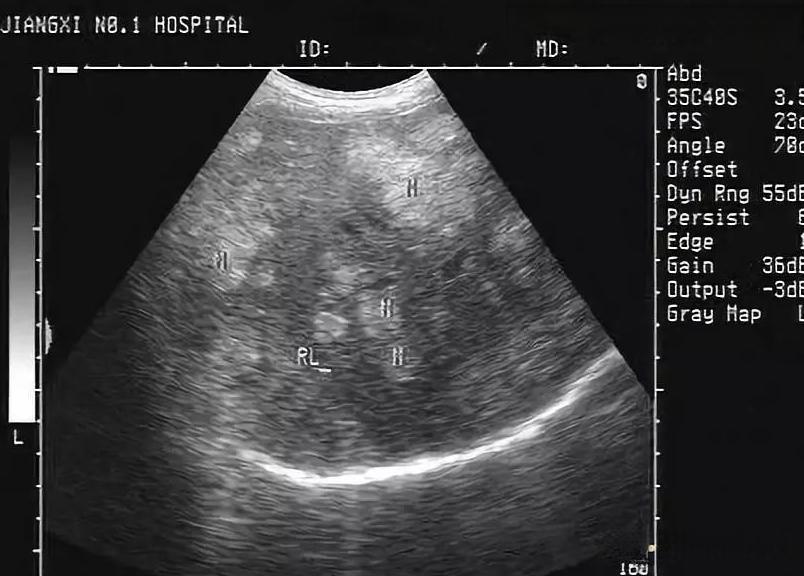

体检报告上出现“肝血管瘤”这几个字,往往会让人紧张不安。但实际上,肝血管瘤是肝脏最常见的良性肿瘤之一,大多数情况下并不需要特别治疗。

诊断肝血管瘤主要依靠影像学检查,如B超、CT和MRI。其中,MRI的诊断准确率最高,可达92%。在极少数情况下,如果影像学检查无法明确诊断,可能需要进行穿刺活检。